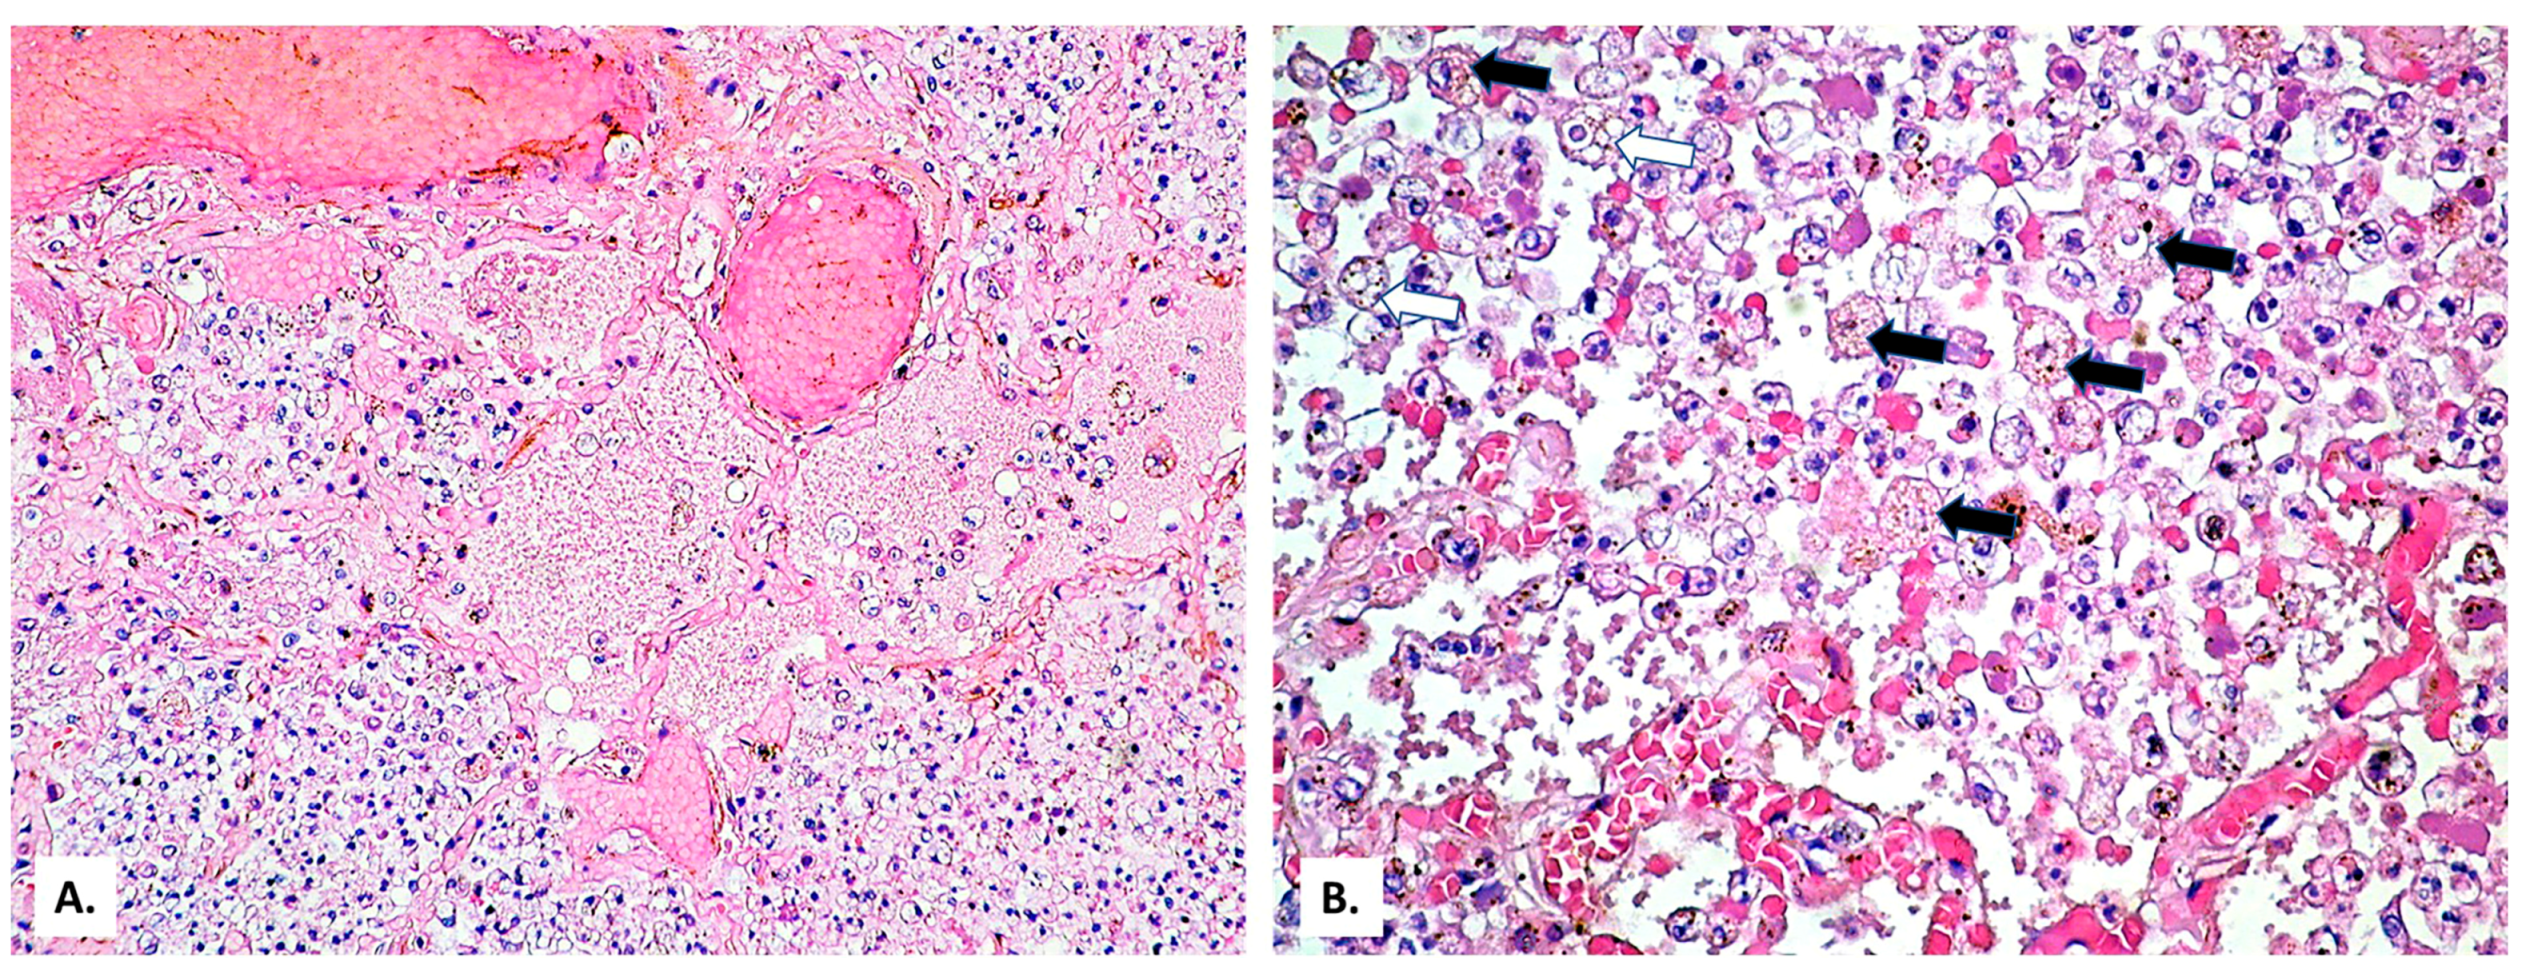

2. Case Presentation